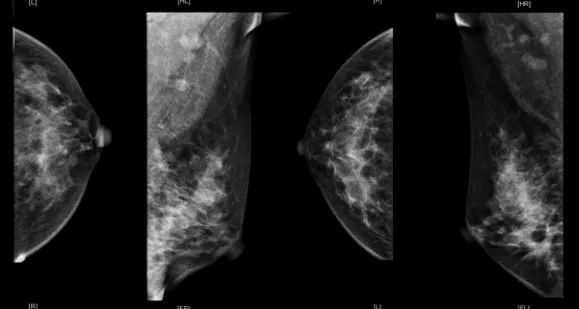

肿块明显缩小,皮肤受侵,但无破溃迹象。乳腺超声(2019年3月4日):左乳癌新辅助化疗后未见明确肿物。乳腺钼钯(2019年3月4日):未见明确肿物。乳腺MRI:左乳下象限肿块较前明显缩小,左腋窝多发淋巴结较前减小。疗效评价部分缓解(partial response,PR)。

乳腺钼钯(2019年3月4日)